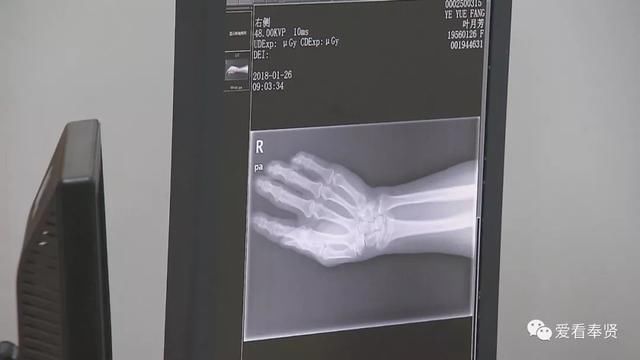

雨雪天急诊骨科病人增多 医院启动应急预案

640x360 - 16KB - JPEG

640x360 - 26KB - JPEG

640x360 - 38KB - JPEG

640x360 - 23KB - JPEG